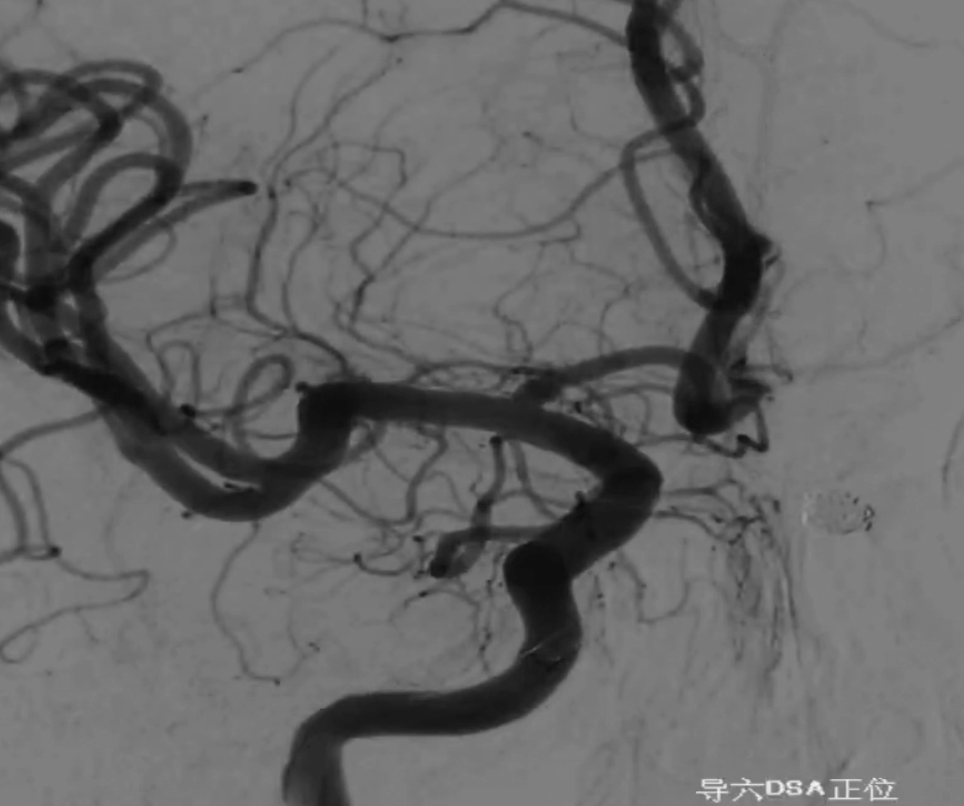

工作位正位造影(图片)

工作位正位造影(视频)

Asahi 0.014微导丝塑形后辅助Echelon 10微导管进入A2远端备支架释放。

Asahi 0.014微导丝导引璞慧 0.017微导管进入动脉瘤内。